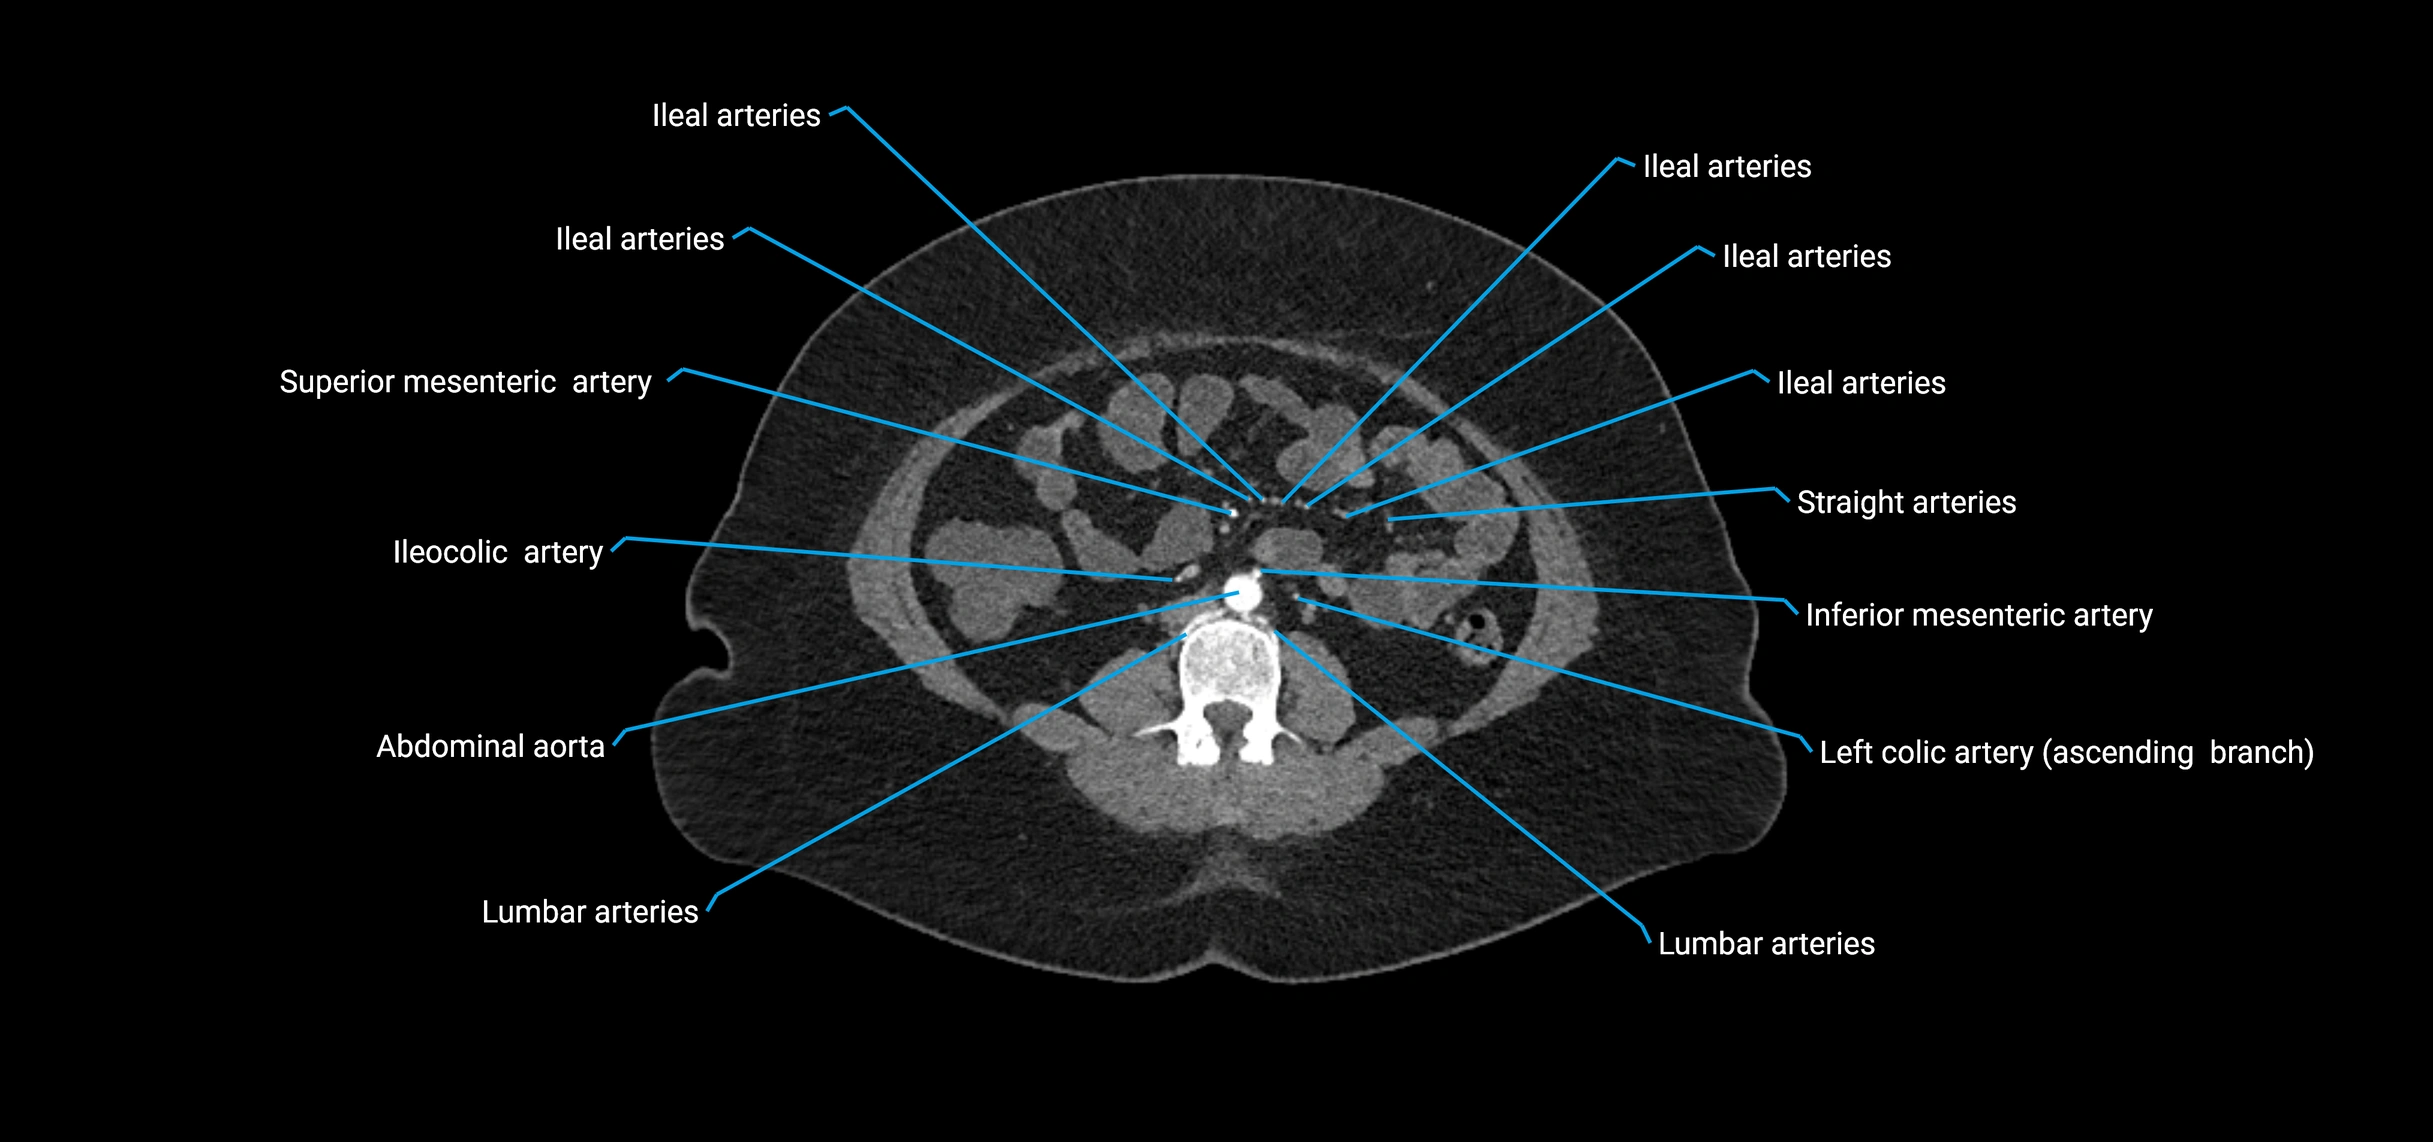

CT images

image